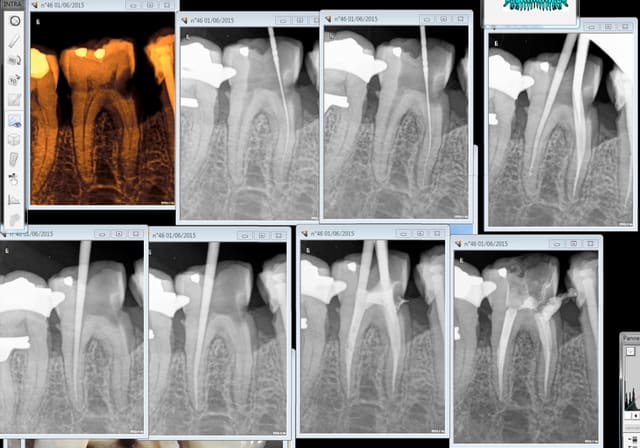

Bon dans ce cas le sc 33 pété sur 45 a été responsable de la carie sur 46. les 2 vont etre passées au taille crayon, c'est l'avantage des composites non indiqués à moyen terme ca fait 2 couronnes au lieu d'une. -))))